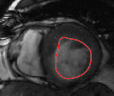

Figures 8 and 9 shows some sample tracking results of the proposed method and Medviso on full cardiac cycles of two different cases on both the LV dataset and the RV dataset. The ground truth (yellow) is superimposed when available. A summary of the results on the entire datasets is shown in Table I. The accuracy with respect to ground truth is measured using average perpendicular distance (APD) and dice metric (DM) for left ventricle, and Hausdorff distance (HD) and DM for the right ventricle. These metrics are chosen since they are the standard ones used on these datasets. Both qualitative and quantitative results show that our proposed method leads to more accurate segmentation of the ventricles and thus leads to less interaction than segmentation propagation schemes in than Medviso.

| initial | ventricle tracked (red - algorithm result, yellow - ground truth) | |||

|---|---|---|---|---|

|

Medviso |

||||

our method |